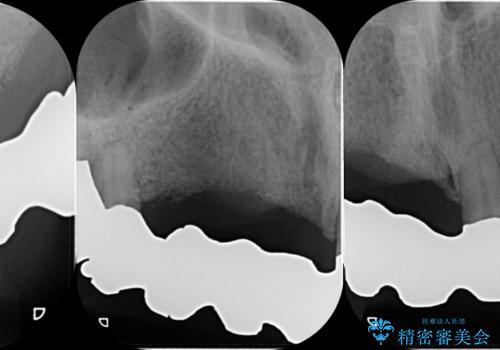

咬合性外傷による歯槽骨吸収 ブリッジ補綴

保存の難しい歯の抜歯、保存できる歯の歯周病治療、欠損部位の歯槽堤形態回復を含めブリッジによる安定した咬合機能回復を計画します。